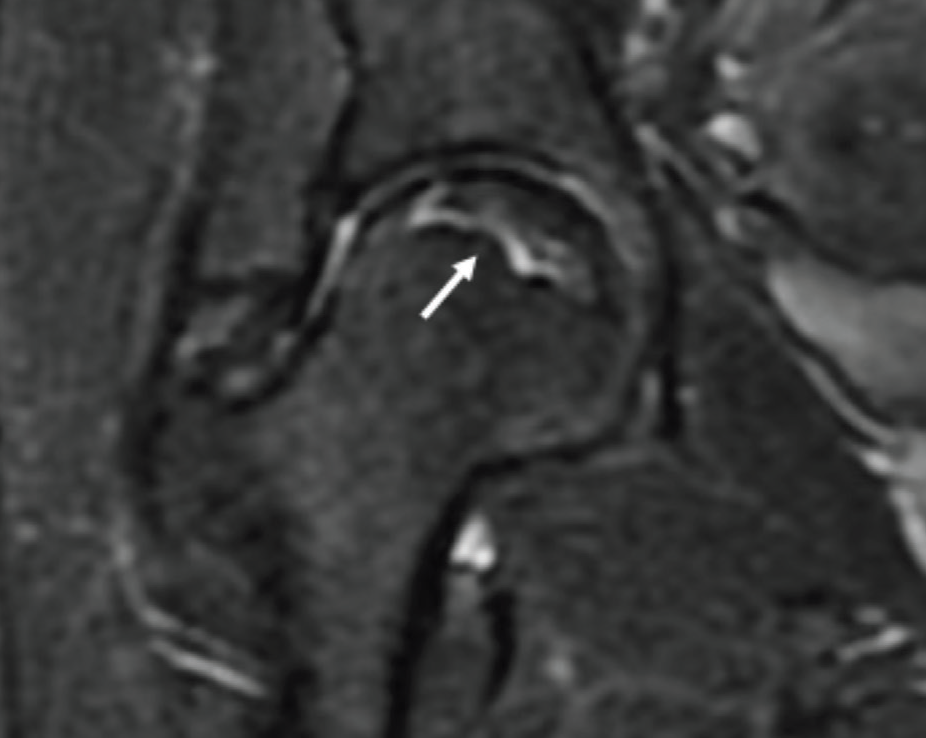

Manyetik Rezonans Görüntüleme (MRG): Röntgende görülemeyen kemik değişiklikleri ve kan akışı bozuklukları MR’da görülebilir. Bu nedenle MR, erken evre avasküler nekroz tanısında kullanılan en hassas radyolojik görüntüleme yöntemidir.

Femur başı avasküler nekrozunda MR’da hilal işareti